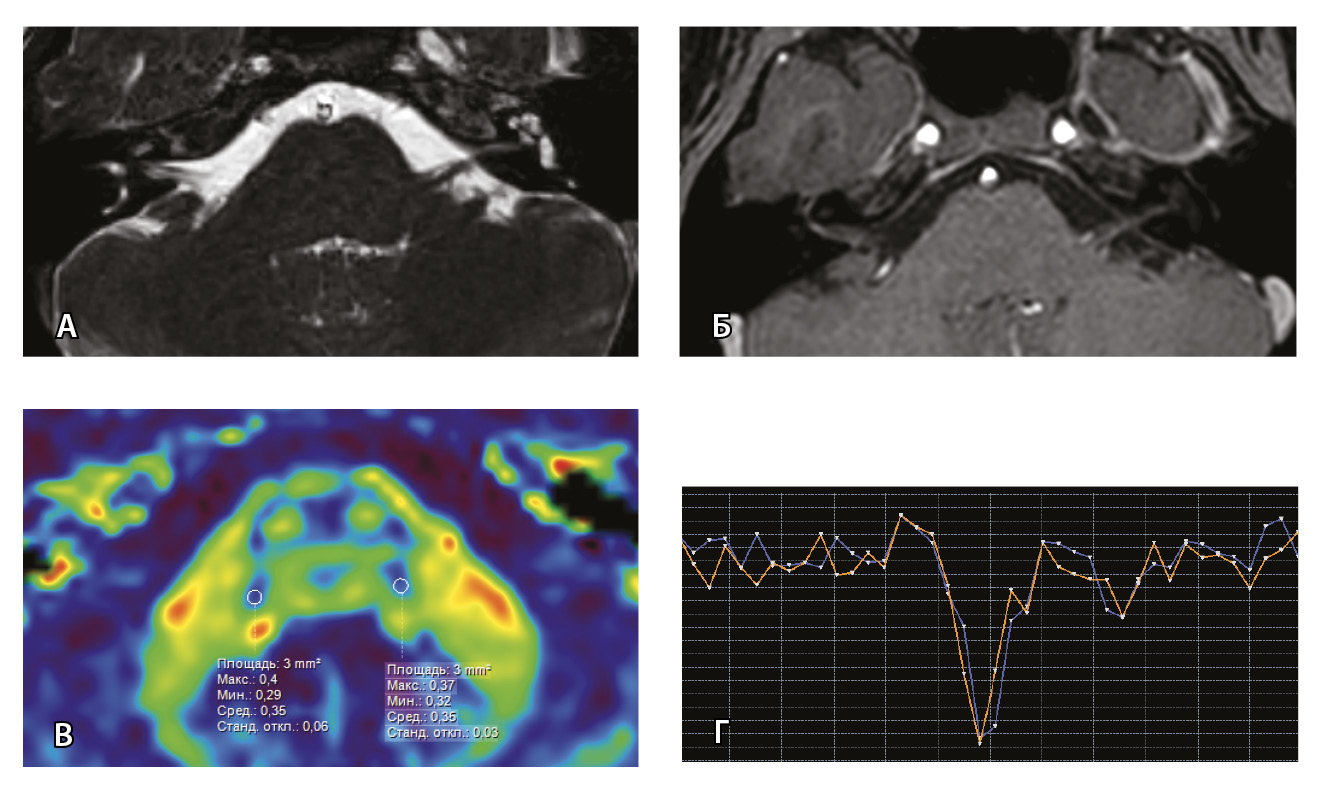

Для наглядности представляем МП-МРТ ребенка без выявленных патологических изменений со стороны черепно-мозговых нервов согласно клиническим данным и при МП-МРТ (рис. 3) Исследование с контрастированием у ребенка без НЛН проводилось по другим показаниям для исключения острого демиелинизирующего процесса.

Рис. 3. Пациент Г. Магнитно-резонансная томография (МРТ) головного мозга: А – прицельная T2-SSFP на область мосто-мозжечкового угла; Б – Т1-взвешенное изображение с контрастным усилением; В – диффузионно-тензорная МРТ (фракционная анизотропия); Г – Т2*-перфузия (здесь и далее графики перфузии отражают зависимость повышения интенсивности МР-сигнала, то есть накопления контрастного вещества (вертикальная ось) от времени (горизонтальная ось), тем самым иллюстрируя основные показатели перфузии – relCBV, TTP, MTT). На изображениях T2-SSFP патологические изменения на уровне прохождения лицевых нервов во внутренних слуховых проходах (А), повышенное накопление вещества корешками лицевых нервов (Б) не определяются. Показатели фракционной анизотропии (В) и Т2*-перфузии (Г) на уровне моторных ядер лицевых нервов симметричны